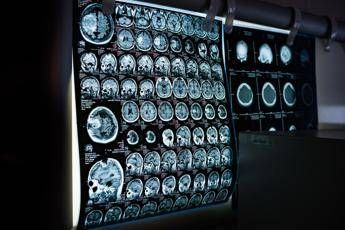

Uno spray nasale testato sui modelli animali potrebbe invertire l'invecchiamento del cervello con sole 2 dosi, riducendo drasticamente l'infiammazione cerebrale, ripristinando le centrali energetiche cellulari del cervello e migliorando così significativamente la memoria. Un processo di ringiovanimento che agirebbe nel giro di poche settimane per durare mesi. E' il risultato dello studio condotto dai ricercatori della Texas A&M University (Naresh K. Vashisht College of Medicine) negli Stati Uniti. Lo spray contiene minuscole particelle biologiche note come vescicole extracellulari (Ev), che agiscono come veicoli di consegna con a bordo un potente carico genetico, i microRna. Le sostanze aggirano lo scudo protettivo del cervello e viaggiano direttamente nel tessuto cerebrale, dove vengono assorbite. Arrivati a destinazione nelle cellule immunitarie residenti nel cervello, i microRna 'spengono' i sistemi noti per essere responsabili dell'infiammazione cronica nel cervello che invecchia. Per spiegare il senso di questo processo, gli scienziati invitano a immaginare il cervello come un motore ad alte prestazioni: nel corso dei decenni questo motore non solo si usura, ma inizia anche a surriscaldarsi. Piccoli 'focolai' di infiammazione covano nelle profondità del centro della memoria, creando una persistente nebbia mentale (brain fog) che rende più difficile pensare, formare nuovi ricordi o persino adattarsi a nuovi ambienti, aumentando al contempo il rischio di disturbi come il morbo di Alzheimer. Questo processo a lenta combustione viene chiamato neuroinfiammazione. E per decenni si è pensato che fosse il prezzo inevitabile dell'invecchiamento. Ma il nuovo studio, pubblicato sul 'Journal of Extracellular Vesicles', suggerisce che l'ondata infiammatoria potrebbe essere reversibile. Il team guidato da Ashok Shetty, distinguished professor dell'ateneo e associate director dell'Istituto di medicina rigenerativa, insieme ai ricercatori senior Madhu Leelavathi Narayana e Maheedhar Kodali, ha sviluppato lo spray nasale e ha verificato che a livello cellulare il trattamento ha ricaricato i mitocondri neuronali, ovvero le centrali energetiche che si trovano all'interno delle cellule cerebrali. La terapia ha dissipato la nebbia mentale e ha anche migliorato fisicamente la capacità del cervello di elaborare e immagazzinare informazioni. "Stiamo ridando vitalità ai neuroni riducendo lo stress ossidativo e riattivando i mitocondri del cervello", evidenzia Narayana. Nei modelli trattati, i test comportamentali hanno confermato i risultati biologici, mostrando notevoli miglioramenti non solo nel riconoscimento di oggetti familiari, ma anche nell'individuazione di nuovi oggetti e di cambiamenti nell'ambiente circostante, in netto contrasto con il gruppo di controllo. "Le malattie legate all'invecchiamento cerebrale, come la demenza, rappresentano un grave problema di salute a livello mondiale – sottolinea Shetty – Quello che stiamo dimostrando è che l'invecchiamento cerebrale può essere invertito, aiutando le persone a mantenere la mente lucida, a rimanere socialmente attive e a non subire il declino cognitivo legato all'età". Lo studio suggerisce un'ampia applicabilità dello spray. I risultati del trattamento, illustra Shetty, "sono stati coerenti e simili in entrambi i sessi". La modalità di somministrazione "è uno degli aspetti più interessanti del nostro approccio", commenta Kodali. "La somministrazione intranasale ci permette di raggiungere e trattare il cervello direttamente, senza ricorrere a procedure invasive". Quanto agli effetti, quella che si osserva è "l'attivazione dei sistemi di riparazione del cervello, che guariscono l'infiammazione e si rigenerano", suggerisce Shetty. Sono ovviamente necessarie ulteriori ricerche per confermare questi risultati, ma Shetty e il suo team hanno già depositato un brevetto negli Stati Uniti per la terapia. Il lavoro è stato portato avanti con il sostegno del National Institute on Aging (Nia).